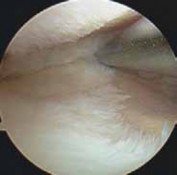

1. A routine diagnostic arthroscopy is performed.

2. The status of the lateral compartment is confirmed.

1. If unexpected lateral compartment osteoarthritis or chondral defects are found, off-loading the knee into that compartment may be detrimental to the longterm results of the surgery (

TECH FIG 1

).

3. The status of the patellofemoral compartment also is confirmed.

1. Significant patellofemoral arthritis (especially of the lateral patellar facet and lateral trochlea) can be ex-

acerbated with an HTO. Such arthritis also can be detrimental to the long-term results of the surgery.

TECHNIQUES

1. Meniscal tears are débrided back to a stable base.

2. Chondroplasty or marrow stimulation is now performed. If the osteotomy is being performed together with a cartilage restorative procedure (eg, autologous chondrocyte implantation), the osteotomy is performed first and then the restorative cartilage procedures are performed, to minimize any trauma to the newly implanted pe-riosteal covering or injected cartilage cells. TECH FIG 1 • A. Arthroscopic image of the medial compartment. Note the bone exposed on the medial femoral condyle and tibia. B. Arthroscopic image following use of a microfracture technique. On entering the lateral compartment, an unexpected cartilage lesion was found on the lateral femoral condyle. Offloading the mechanical axis into the lateral compartment that already is degenerated is a

A B contraindication to the procedure.